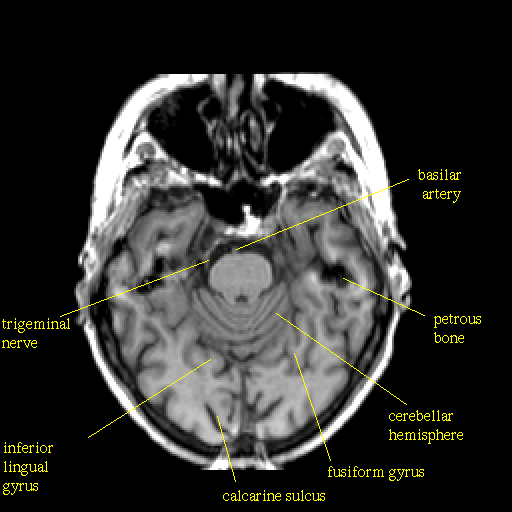

T1-weighted structural MR: Slice 17

Slice 17